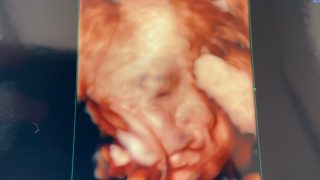

名前が決まりました!!

来週で妊娠8ヶ月になる手抜き主婦ですが、 ついに!我が子の名前が決まりました!! 妊娠5ヵ月の時に女の子と分かったのですが、 主人と意見が合わず、なかなか決まりませんでした(笑) 名づけで気にすること・・・ 性別は女の子・・・...

妊娠7ヶ月~変化~

※妊娠関連の記事になります。 妊娠7ヶ月になってからの変化 現在妊娠7ヶ月(26w6d)なのですが、 妊娠7ヶ月に入ってからの変化をご紹介していきたいと思います。 健診が2週間おきに! まず、妊婦健診が2週間おきになりました! ...